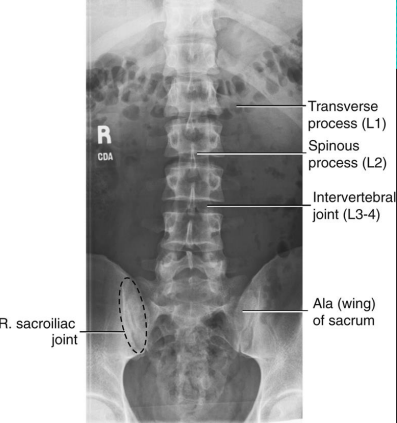

AP L-Spine: Eval Criteria

Centered at the crest (or 1.5” above) to include T12 to sacrum

No rotation

Open intervertebral joint spaces

How does rotation manifest on an AP L-spine?

SI joints unequal from spinous processes

Spinous processes shifted to either side of midline of vertebral column

Transverse processes of unequal length

AP L-Spine: Is this Image Good?

No.

Slight right rotation evidenced by spinous processes projected to the left of midline

T12 is clipped due to low centering at the crest

Needs collimation

Needs marker